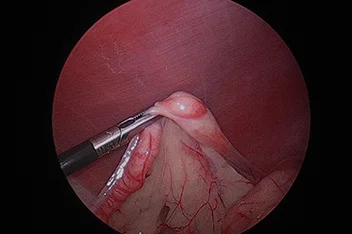

흉강경

복강경과 유사하게 최소 절개를 통해 흉강 수술을 진행하게 됩니다.

작은 구멍으로 카메라 포트가 진입하여 수술 부위를 시각화하고 진단과 치료를 진행할 수 있습니다.

흉강에서는 탐색과 조직생검을 통해 확실한 진단에 도움이 됩니다.

심낭수 치료를 위해 심낭막절제술, 최소침습 폐엽절제, 유미흉의 치료를 위한 흉관결찰(Thoracic duct ligation) 등이 진행될 수 있습니다.

흉강경심막절제술 (Preicardiectomy)

흉강경흉관결찰 (Thoracic duct ligation)

* 리본동물의료센터 케이스 사진으로 무단 복제 및 도용을 금지합니다.